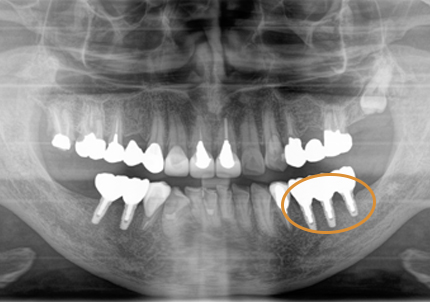

18.インプラント埋入後 パノラマレントゲン

3.前回治療後5年経過(2021年2月)

【左下ブリッジ5番6番歯根破折の為要抜歯】

【左下5番ソケットシールドテクニック】